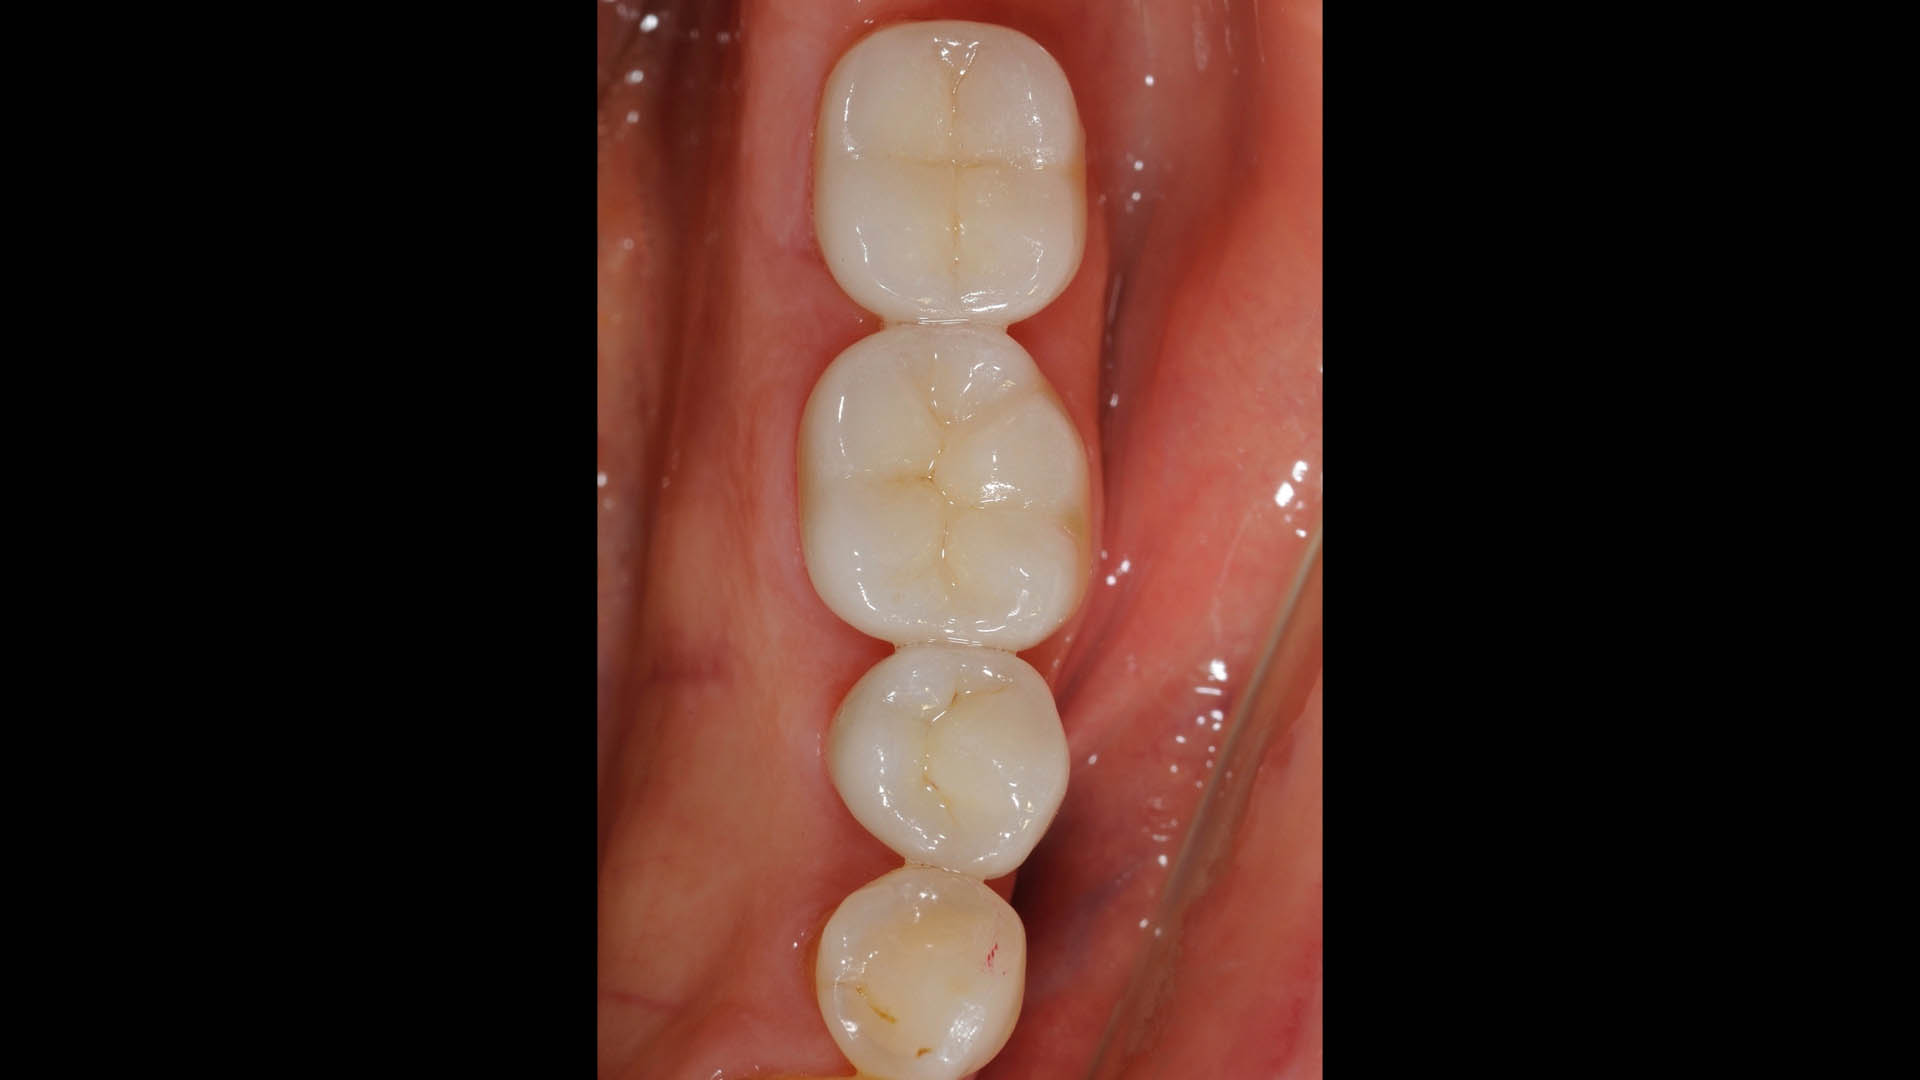

Take a glimpse into the magic of Coral Gables Dentistry through our before and after pictures. See firsthand the incredible smile makeover transformations that have brought confidence and joy to our patients.